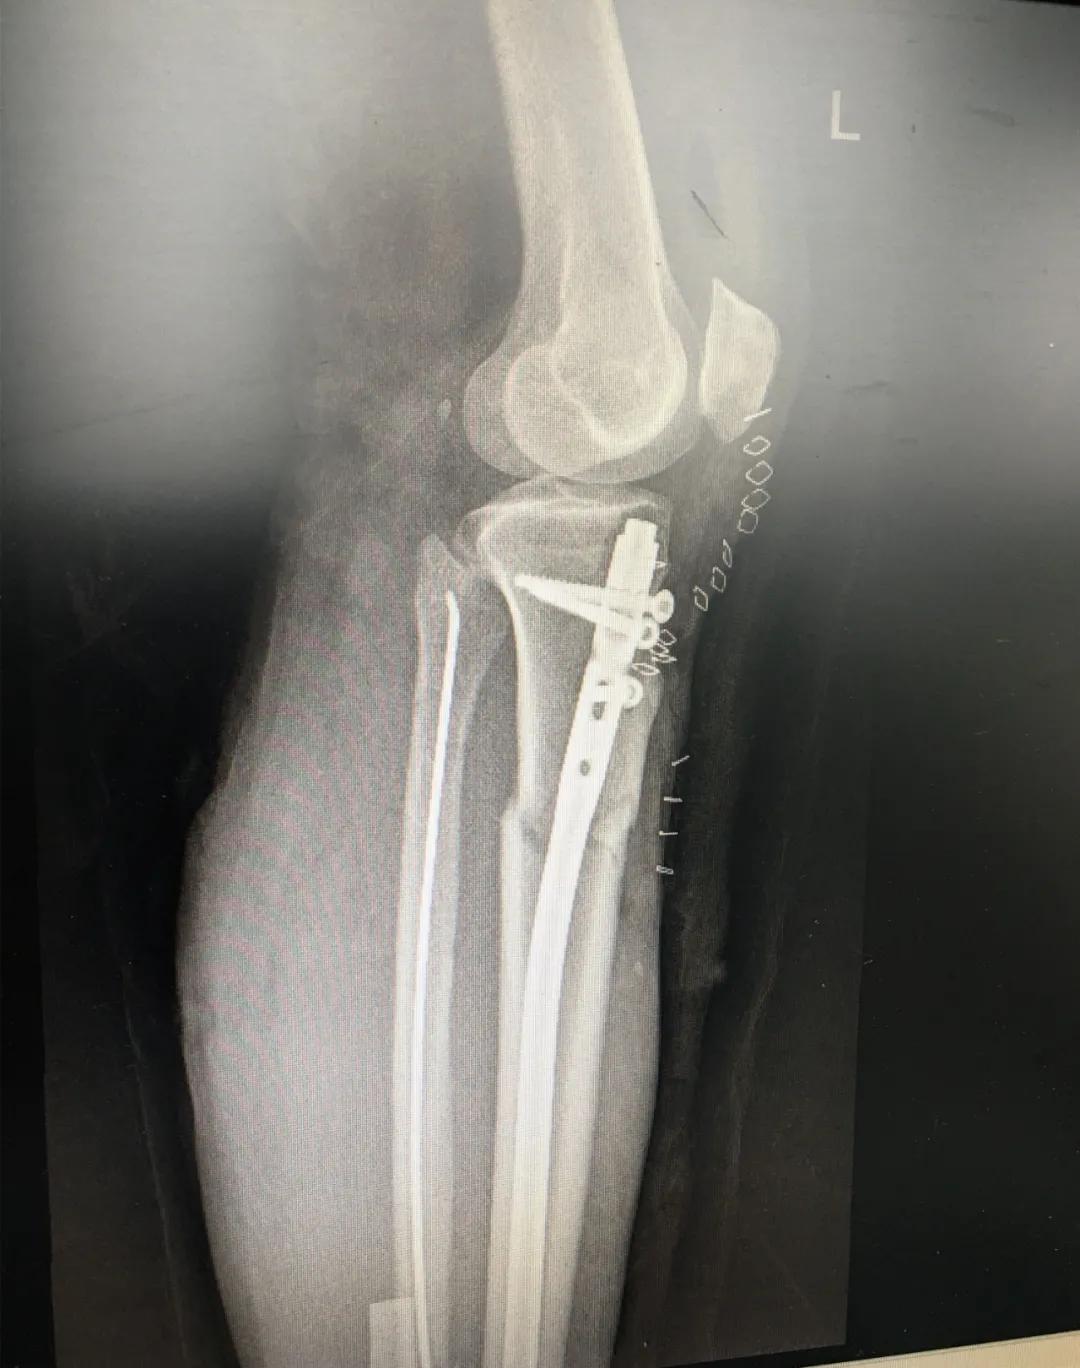

刘阿姨半个月前骑电动车时与小轿车相撞,导致了左胫腓骨粉碎性骨折,小腿骨碎成了三段。"然而,在术前丈夫周先生对刘阿姨的治疗却拿不定主意。“我妻子身上有多种基础疾病,患高血压15年,糖尿病也有8年多了。这里的诊疗技术,能不能保障手术的安全?手术前,我们家属的心中确实也很忐忑!"由于对我院创伤技术水平不太了解,周先生已经准备要转院治疗。

为患者实施的骨折微创复位固定技术是创伤骨科的特色技术。相较传统手术需要20公分的切口,微创手术只需要3公分左右。闭合复位髓内钉固定技术、经皮插板内固定技术(mippo技术)、闭合复位空心螺钉固定技术等一系列的微创复位固定技术,具有切口小、出血少、创伤小、愈合快、疤痕小等优点,骨折术后并发症明显降低,患者还可以早期负重功能锻炼。